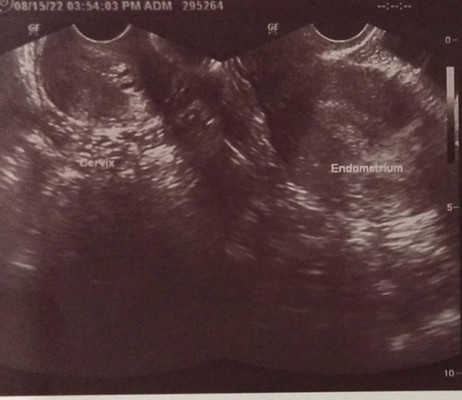

Hello everyone! Just want to share my experience. Aug.15 - Nagpa check-up ako sa OB kasi nga almost 1 month na delay period ko. I told the doctor that all my PTs are negative but I have sore boobs. (I didn't mention that I have some of those pregnancy symptoms). And sabi nya thick lang daw lining nga uterus ko. I asked her kung ano possible reasons why thick ang lining and she said kasi di pa ako nag-menstruate. Aug. 17 - Nakaramdam ako ng slight pain sa abdomen. So I decided na mag PT ulit the following day. Aug.18 - Nag-PT ako at yun nga..faint positive. Di ako makapaniwala cause we're TTC for almost 2 years na and all my previous PTs are negative. As in, that was the first time na nagka result ng ganun ang PT ko. Aug.19 - Retested and the result was the same. Faint positive. Fast forward... Here's the sad part. 😣 Aug. 21 - It was at night ng makita ko may spotting sa underwear ko. It's not bright red, parang pink lang. I thought it's normal at mawawala lang and so natulog na lang ako. Aug. 22 - I woke up early kasi magpapa check-up ako but sad to say, pag-ihi ko sumabay din yung dugo ko. Di ko alam kung menstruation ba yun or ano. 😭 ----------------- Sobrang saya na sana namin ng asawa ko pero ganito lang nangyari. Palagi naming dasal na mabiyayaan kami ng anak pero di pa talaga time. 😭 Sobrang sakit lang. 😭😭😭